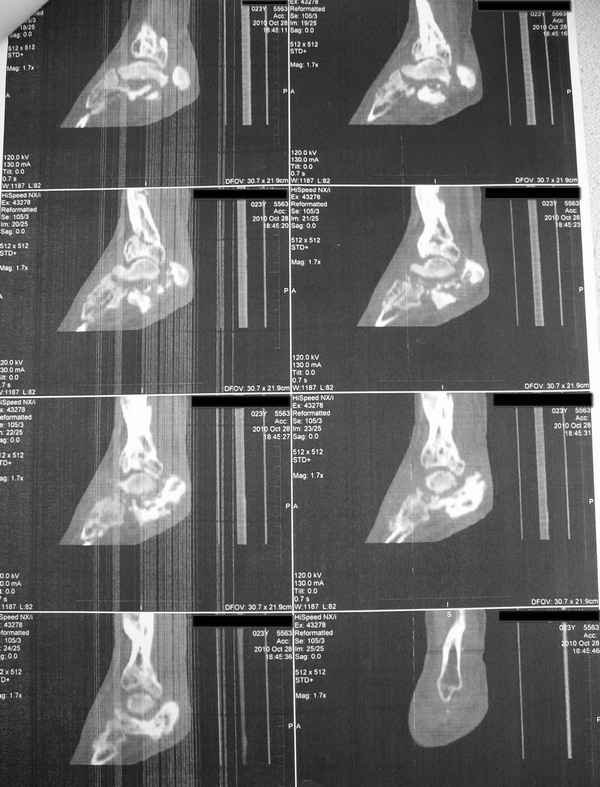

Молодая девушка со сросшимися многооскольчатыми переломами пяток и голеней.Young girl

with fractures of the calcaneus

Больная Н., 25 лет, падение с высоты (2008 г.). Жалобы на боли в области голеностопных

суставах, в области пяток при ходьбе. Лечилась в аппаратах внешней фиксации по поводу

открытых оскольчатых переломов обеих голеней, переломов пяток. Далее по поводу

несросшихся переломов голеней ЧКОС аппаратами внешней фиксации. Переломы срослись,

аппараты демонтированы весной 2010г. В левой пяточной области в месте проведения спицы

имеется сукровичное отделяемое. При ревизии гноя нет. Чем помочь девушке?

Patient N., age

25, falls from heights (2008). Complaints of pain in the ankles, in the heel when walking. She

was treated by external fixation on open comminuted fractures of both legs, fractures of the

calcaneus. Then she was treated by external fixation from nonunion of both legs. Now

fractures are fused, apparatuses removed in the spring of 2010. How to help a girl?